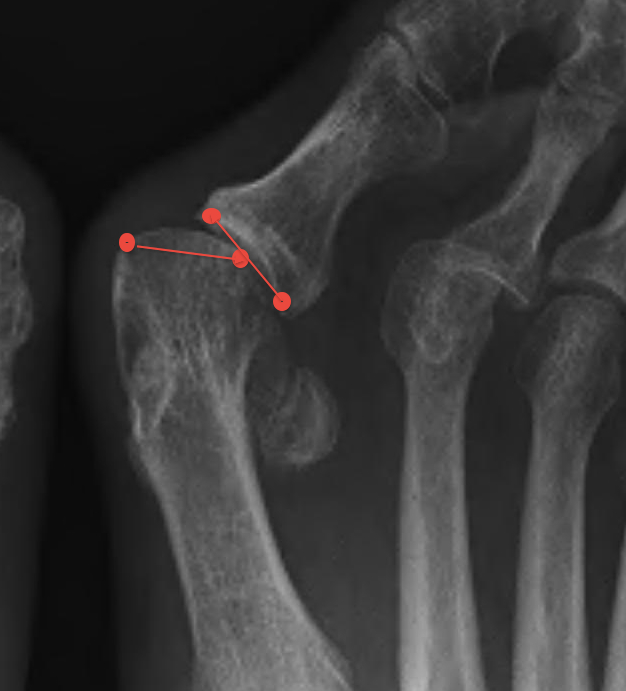

Other

| Joint congruence | Sesamoid subluxation | TMT joint obliquity |

|---|---|---|

|

Dots on articular surfaces - metatarsal head - base P1 |

Amount of lateral sesamoid uncovered |